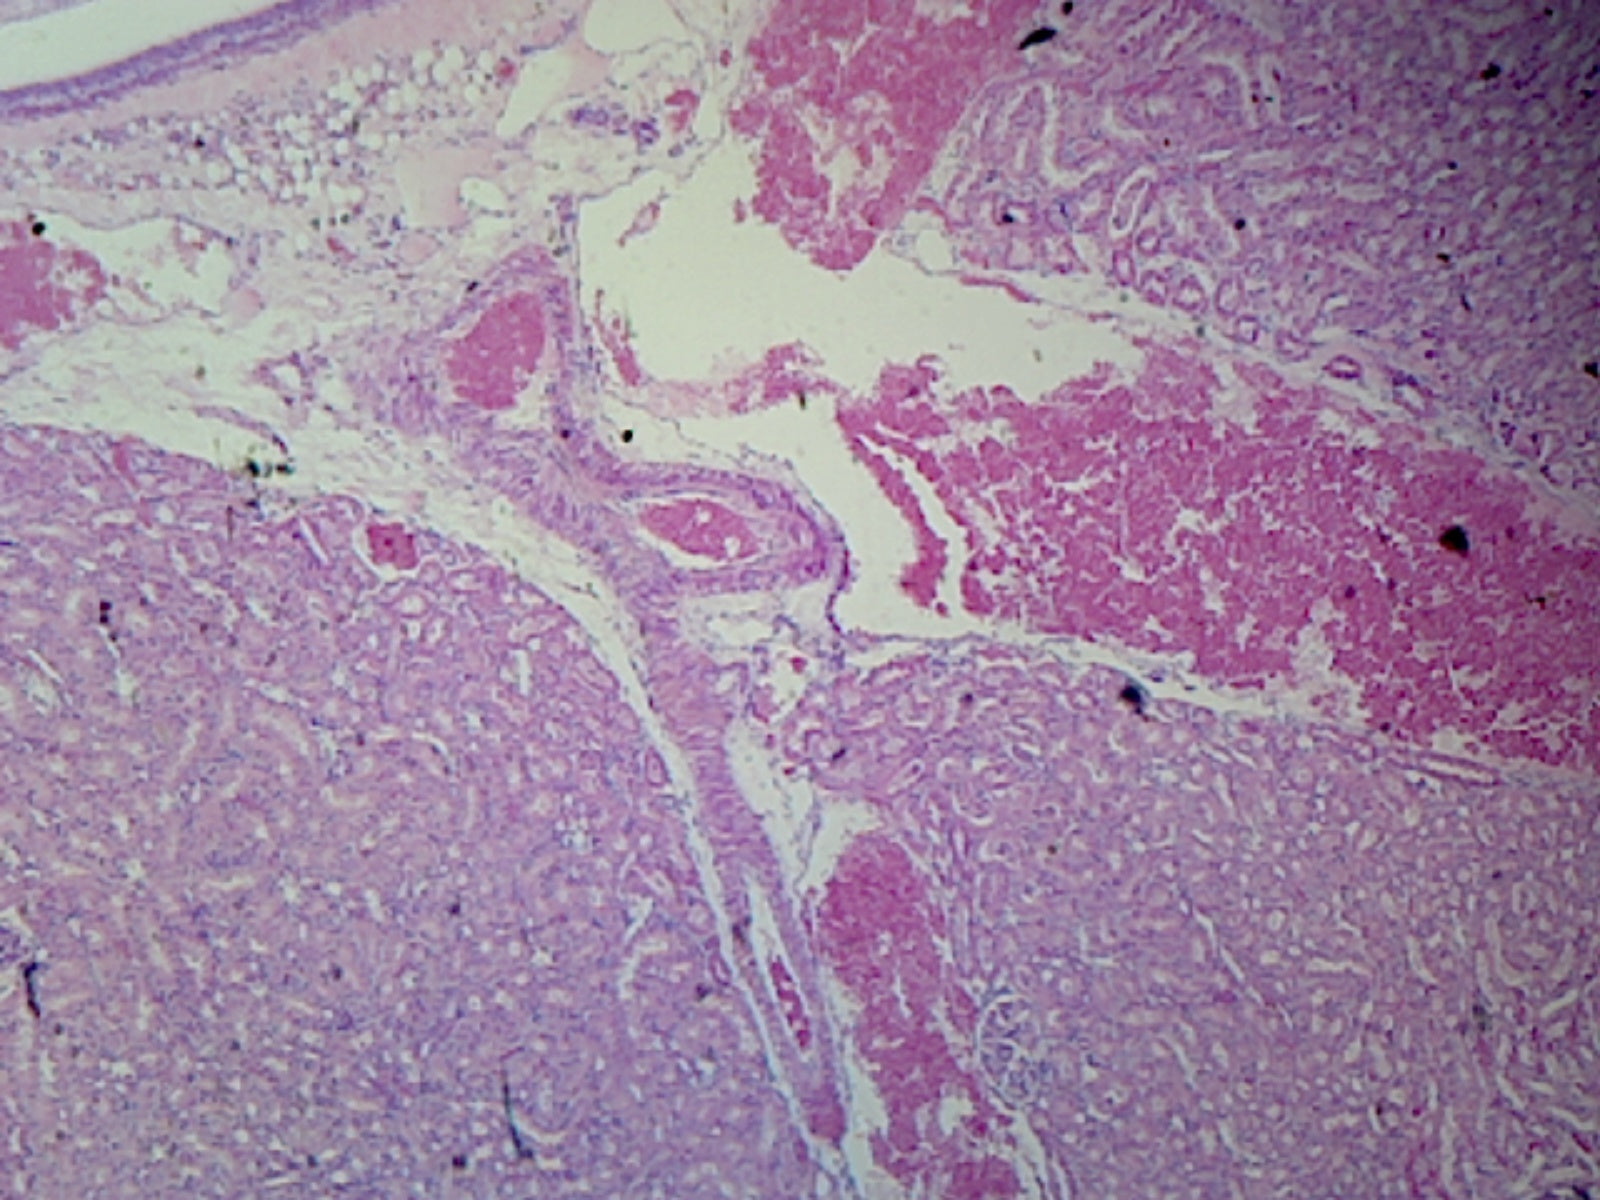

Histology is the branch of biology dealing with the study of organic tissues, especially on the microscopic level.

This slide is a longitudinal section of a kidney from a mammal. It shows the renal pelvis, calyces, cortex, and medulla.